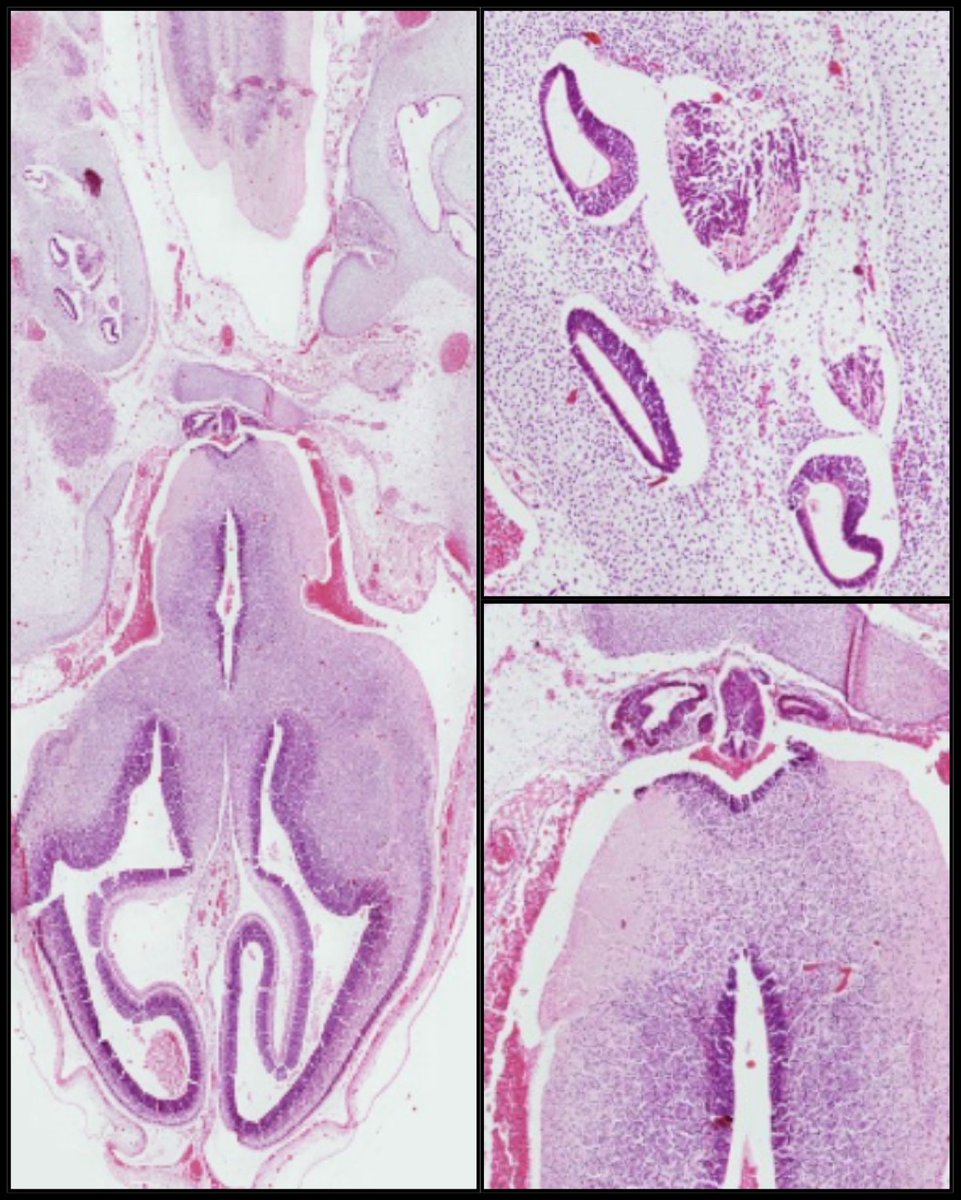

Microscopio Virtual - Histología y Embriología @histoemb , Facultad de Medicina, Universidad de la República, Uruguay. Desarrollado por @ernestomiquel